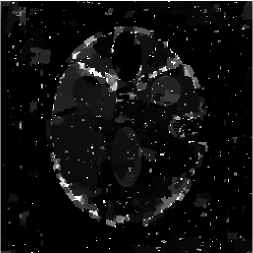

Figures 4 and 5 present visual reconstruction results of the SL phantom and the FB phantom, respectively, both under high additive Gaussian noise (). In particular, Figure 4 is to recover the SL phantom using 7 radial lines. The model has severe streaking artifacts due to this extremely small number of data obtained on the radial lines. The minimization on the gradient yields significant improvements over the baseline model (TV). The proposed algorithm outperforms the previous ADMM approach at the outer ring and boundaries of the three middle oval shapes, which are more obvious in the difference map to the ground truth. On the other hand, the FB phantom has finer structures and lower image contrast compared to the SL phantom. As a result, it requires 13 radial lines for a reasonable reconstruction. As we observe in Figure 5, the overall geometric shapes are preserved. At the same time, many speckle artifacts appear in the reconstructed images by no matter which algorithm is used.